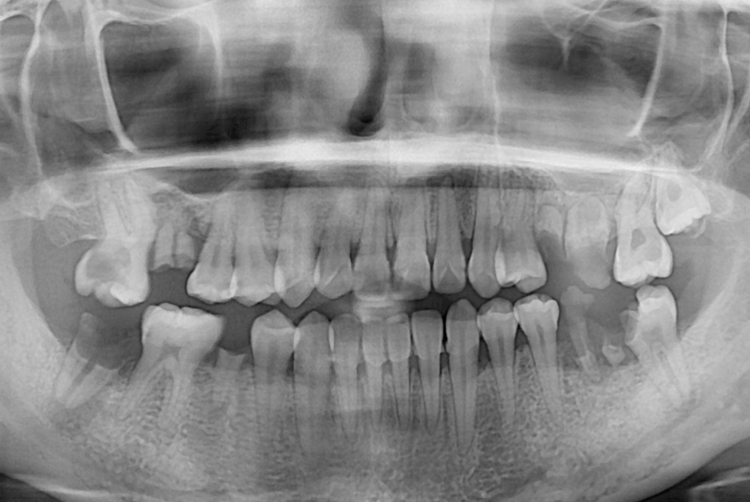

523 신미란_후.jpg

치료후 : 2018-03-22

세종치과는 많은 환자와 다양한 케이스를 바탕으로 항상 편안한 임플란트 수술을 제공하고자 노력하고,

오래동안 튼튼히 쓸 수 있는 임플란트 수술을 가장 큰 목표로 삼고 있습니다